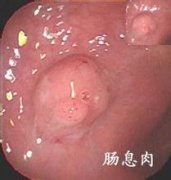

在我们的肠道王国里,住着一群沉默的“不速之客”——结肠息肉。它们最初可能只是肠道黏膜上一颗不起眼的“小肉球”,像恶作剧般悄悄探出脑袋。可别以为这只是肠道的“小疙瘩”,若放任它们在体内“野蛮生长”,一场惊心动魄的“肠道危机”可能正悄然酝酿。

腺瘤性息肉(尤其是直径>1cm)具有明确恶性倾向,长期存在会导致细胞异常增生及基因突变,最终发展为结肠癌。

息肉数量越多、体积越大,癌变风险呈指数级上升,需尽早干预。